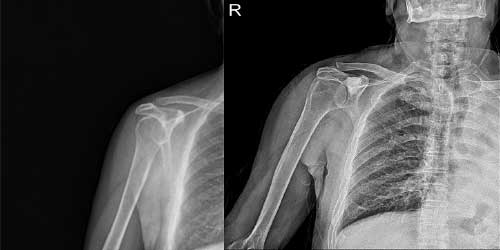

Omurga metastazı, kanserin ilk olarak iç organlarda gelişip daha sonra omurga kemiklerine yayılması sonucu oluşan bir durumdur. Çoğunlukla kan yoluyla sıçrayan bu tür metastaz, hastalarda sırt ve bel ağrısı gibi şikayetlerle kendini gösterir. Erken teşhis ve uygun tedavi yöntemleri, hastaların yaşam kalitesini artırmada kritik bir rol oynar.

Tedavide başarıyı artıran en önemli etkenlerden biri ameliyat öncesi iyi bir hazırlık ve cerrahi planlama yapmaktır. Her şeyden önce tanı doğru konmalı. Bunun için hasta iyi dinlenip, detaylı muayene edildikten sonra tetkikleri dikkatli incelenmelidir.